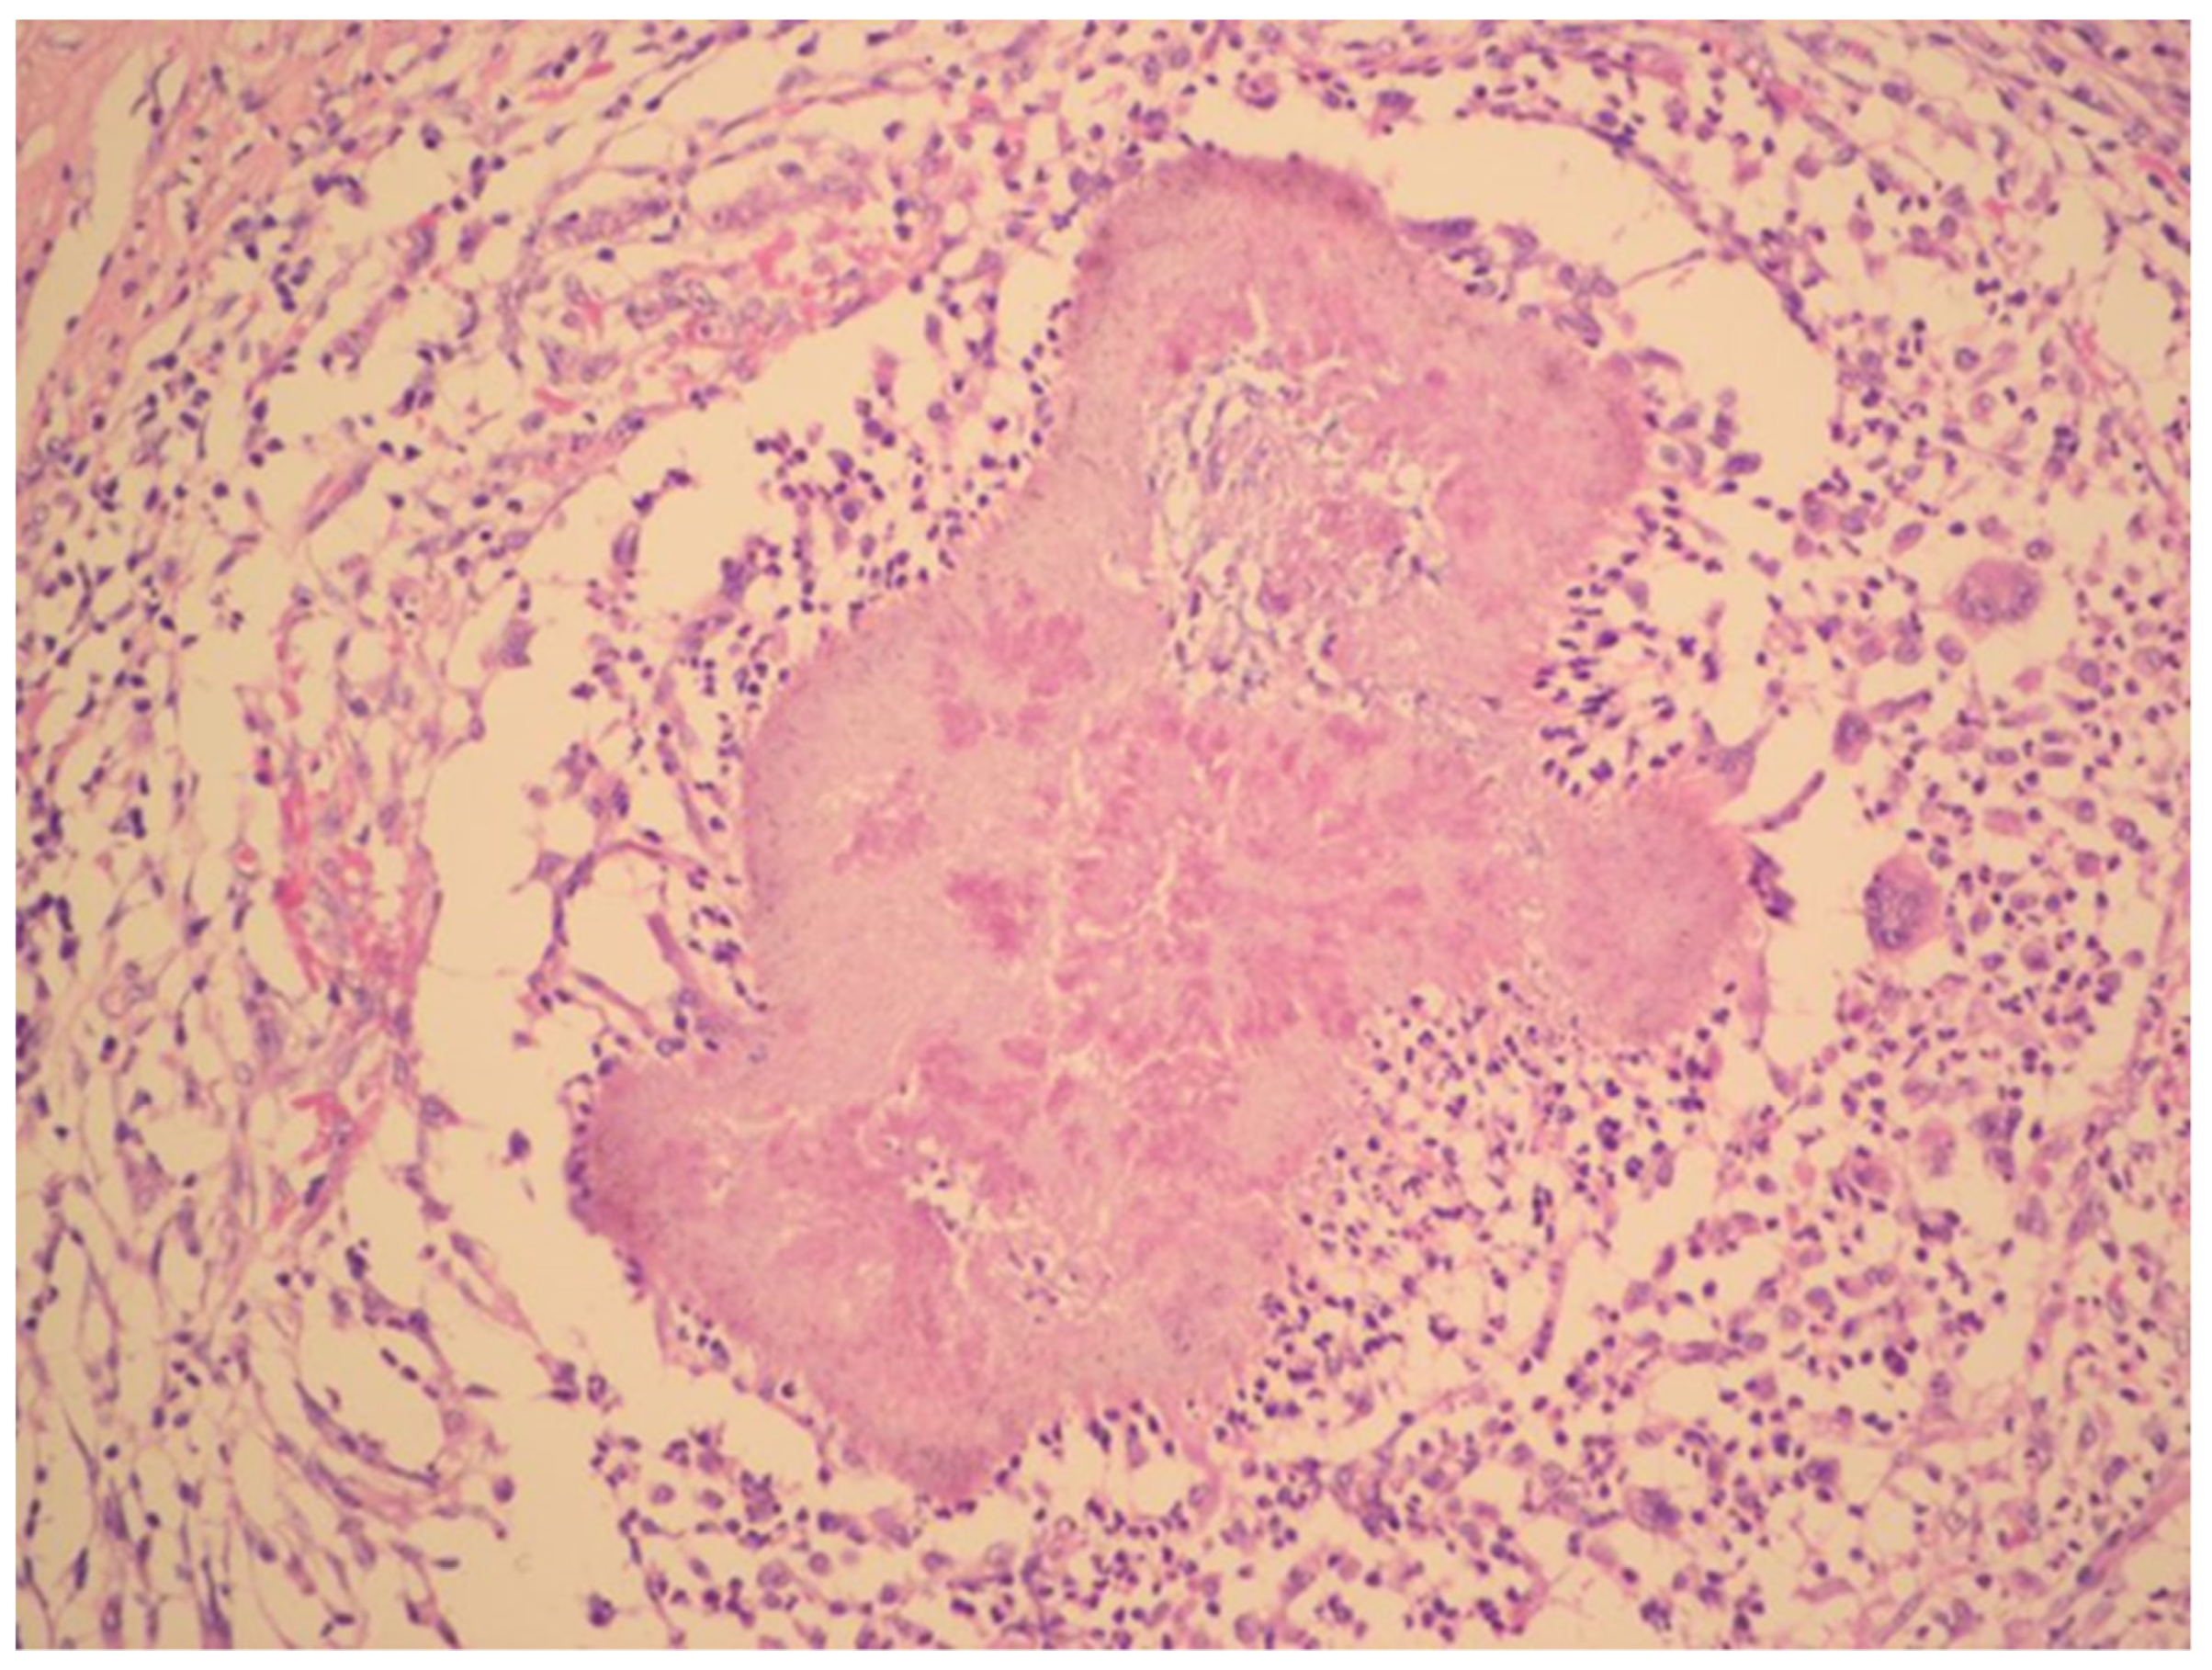

CT scan showed ascites, an enlarged right ovary with a parauterine non-homogenous mass 8 × 5 cm in size containing gas, bilateral hydronephrosis, ischaemic foci in spleen, multiple bilateral tiny nodules in the lungs with mainly subpleural distribution resembling miliary tuberculosis or multiple emboli, multiple liver lesions described as signs of Budd–Chiari’s syndrome due to the inferior vena cava thrombosis, and right hepatic vein thrombosis (Figure 1 and Figure 2).

Figure 1. Pelvic CT scan shows ascites, enlarged right ovary (white arrow) and a gas-containing non-homogenous mass adhering to the uterus (black arrow).